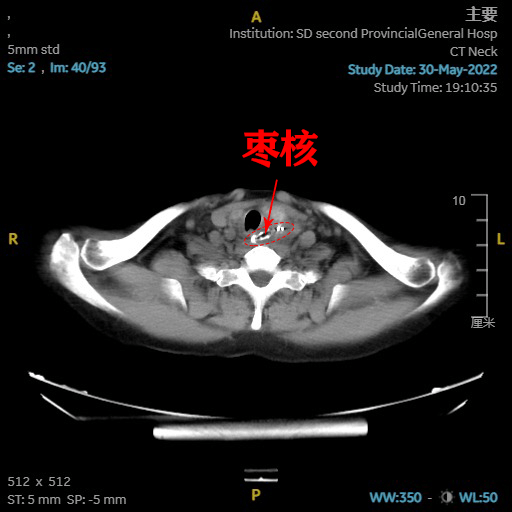

咽喉科主任崔鹏为赵先生安排了ct检查,结果显示,枣核卡在了食管上段

图片尺寸512x512